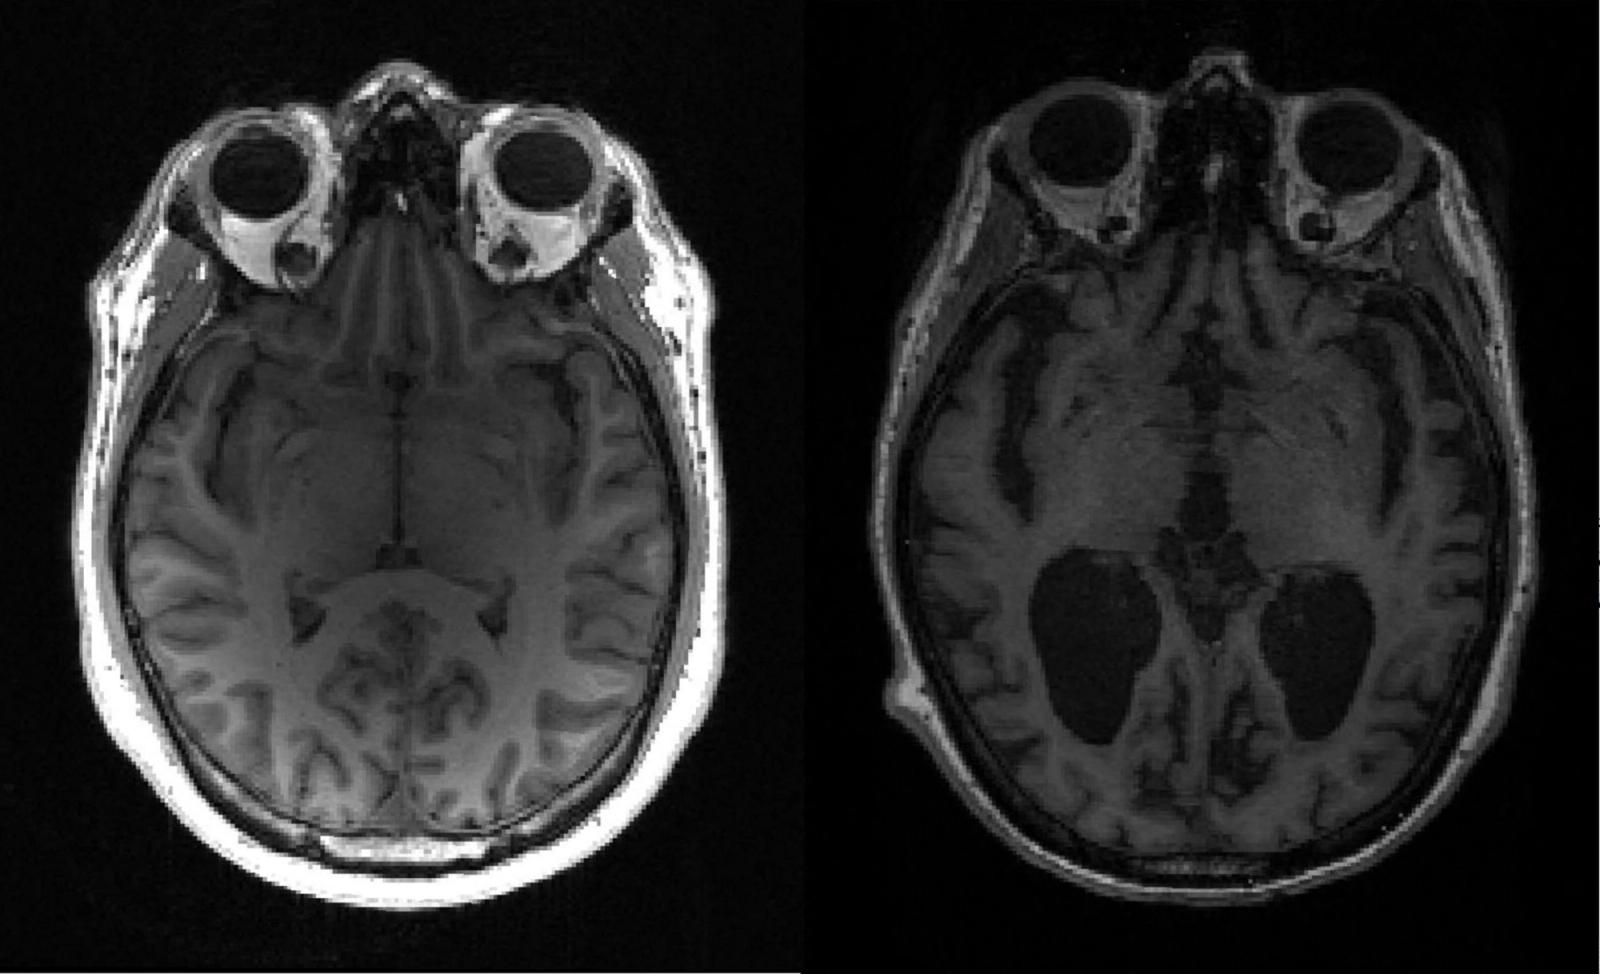

Vi er etter hvert blitt skeptiske til meldinger om mulige fremskritt i kampen mot Alzheimer. Det har vært litt for mange optimistiske beskjeder, som bare har ført til falske forhåpninger. Men tyske og kinesiske forskere fra henholdsvis Heidelberg og Shandong har nå funnet en angrepsvinkel som skiller seg fra tidligere forsøk. Det har også vist seg lovende i behandling av mus med Alzheimer.